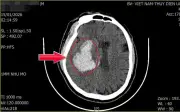

Đề xuấtTăng huyết áp là 'kẻ giết người thầm lặng', không triệu chứng rõ ràng nhưng âm thầm gây tổn thương tim mạch, dẫn đến nhồi máu cơ tim, đột quỵ ngay cả ở người trông khỏe mạnh.

Đề xuấtNắng nóng kéo dài khiến nhiều ca say nắng, sốc nhiệt nhập viện tại Phú Thọ. Có bệnh nhân hôn mê sâu, suy đa tạng sau khi làm việc ngoài trời. Cảnh báo nguy cơ từ lao động dưới nắng gắt.